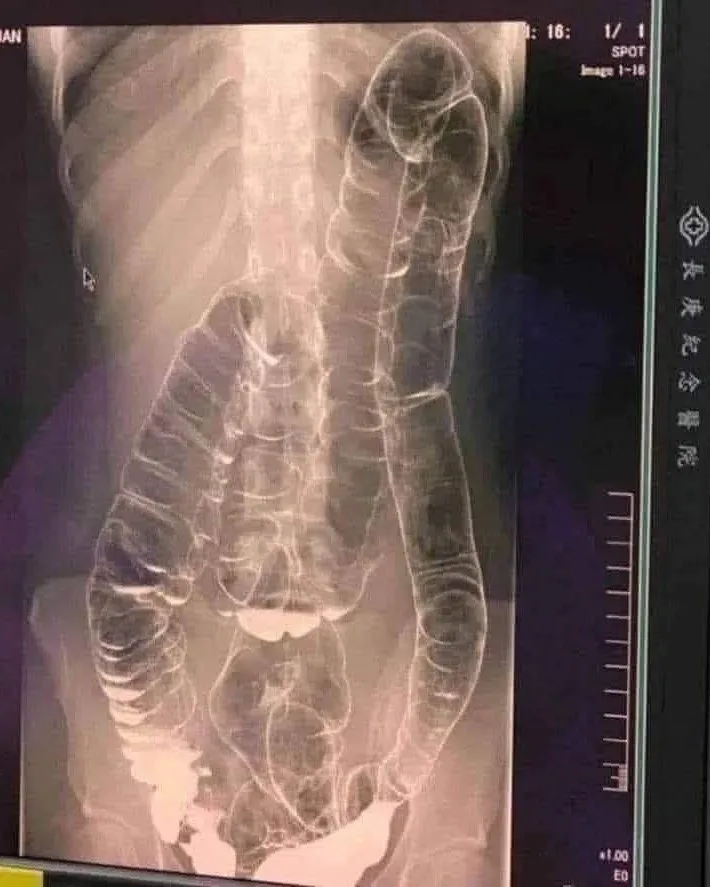

When waste accumulates in the colon due to an inefficient digestive system, it causes severe discomfort and bloating. Over time, the colon expands beyond its normal size, struggling to contain the excessive buildup of feces. In this case, medical imaging revealed a severely distended colon that had enlarged so much it reached up toward the chest, dangerously close to the heart. The stretching had nearly erased the colon’s natural folds and wrinkles, essential for its proper function. Left untreated, this condition could have led to life-threatening complications.